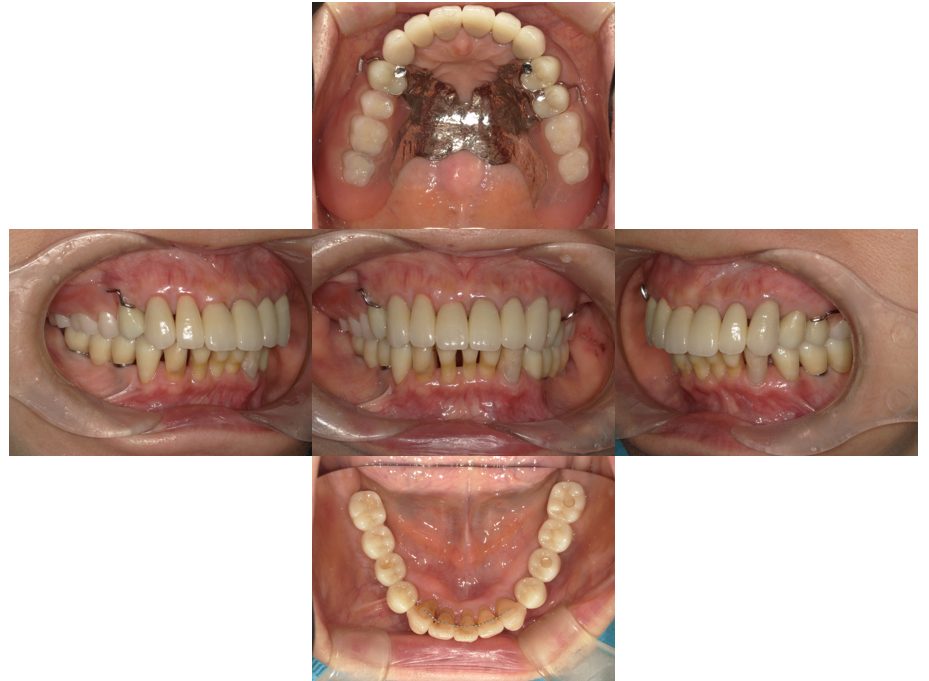

| 主訴 | 50代男性 右上の歯と歯茎が痛い。どこで噛んでいいのか分からないので夜も眠れない |

| 治療内容 | 外科矯正治療・インプラント治療・セラミック治療を行いました。 |

| 治療費 | 4,500,000円(税込み) |

| 治療期間 | 4年(矯正治療期間 3年) |

| 治療回数 | 60回 |

| 想定されたリスク | 顎骨の変形があったので、全身麻酔下による外科処置が必要になり、身体的、精神的負担が増す可能性がありました。 清掃状況によっては矯正中にむし歯が発生するリスクがありました。 |